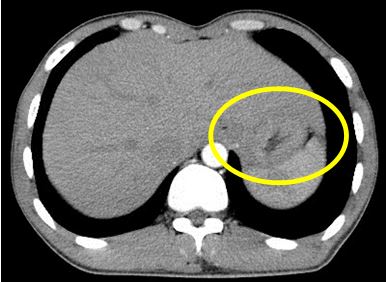

- Nội soi thực quản- dạ dày: U sùi loét tâm vị dạ dày chảy máu, gây hẹp đèn soi khó đi qua, đã bấm sinh thiết tổ chức u làm xét nghiệm mô bệnh học. Kết quả sinh thiết: : Ung thư biểu mô tuyến típ kém biệt hóa

Hình 1: Hình ảnh khối u sùi tâm vị dạ dày qua nội soi